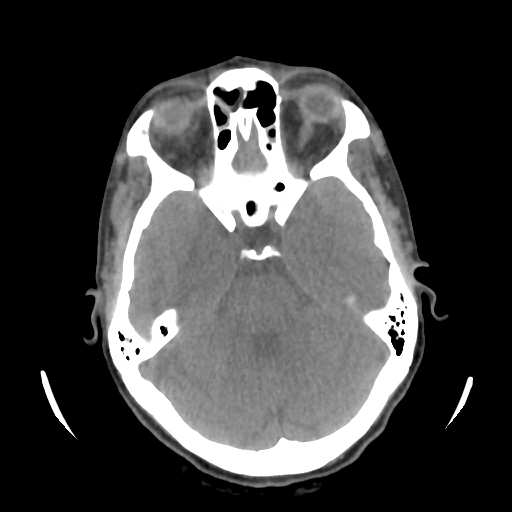

A 33 years old woman with protruding eyeballs & hyperthyroidism since 2 years